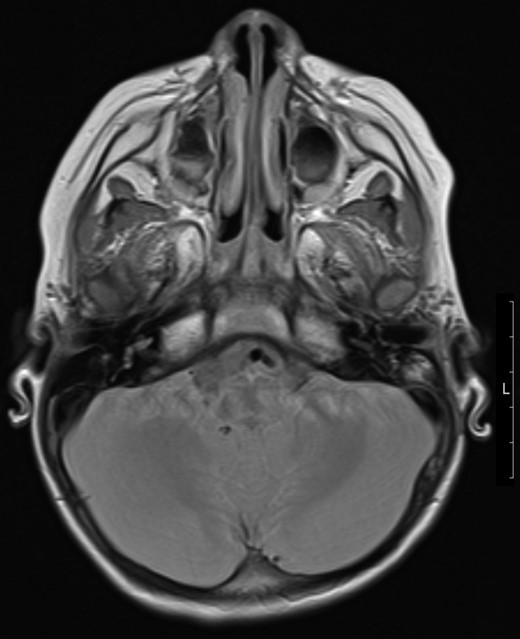

Patient underwent MRI imaging (Day 6 post drainage) which showed near resolution of the epidural and extracranial collection (Fig. 3). Upon review of images it was decided that no further surgical input was necessary, and the patient was discharged with follow up planned within 2 weeks.

Transverse magnetic resonance image 3 months post op showing some residual inflammation within the post-surgical mastoid cavity (white asterisk) and resolution of collection.

Although the patient was responding well to treatment, persistent lethargy and poor appetite resulted in a repeat MRI 3 months after he was initially started on anti-TB medication, which excluded an intracranial collection but revealed middle ear fluid which was subsequently drained by myringotomy and grommet insertion resulting in resolution of symptoms. The patient is currently responding well to therapy, with no clinical signs of recollection.